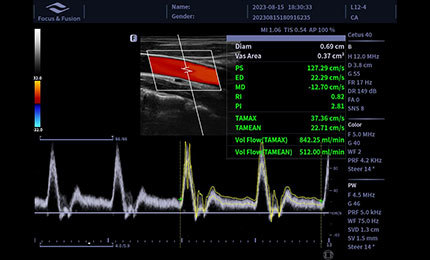

Mierzenie powierzchni naczynia krwionośnego, prędkość przepływu krwi może być automatycznie mierzona przez spektrum, a wyniki objętości przepływu krwi zostaną wyświetlone.